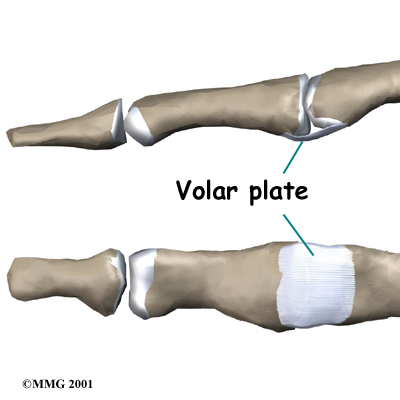

In the PIP joint (the middle joint between the main knuckle and the DIP joint), the strongest ligament is the . This ligament connects the proximal phalanx to the middle phalanx on the palm side of the joint. The ligament tightens as the joint is straightened and keeps the PIP joint from bending back too far (hyperextending). Finger deformities can occur when the volar plate loosens from disease or injury.